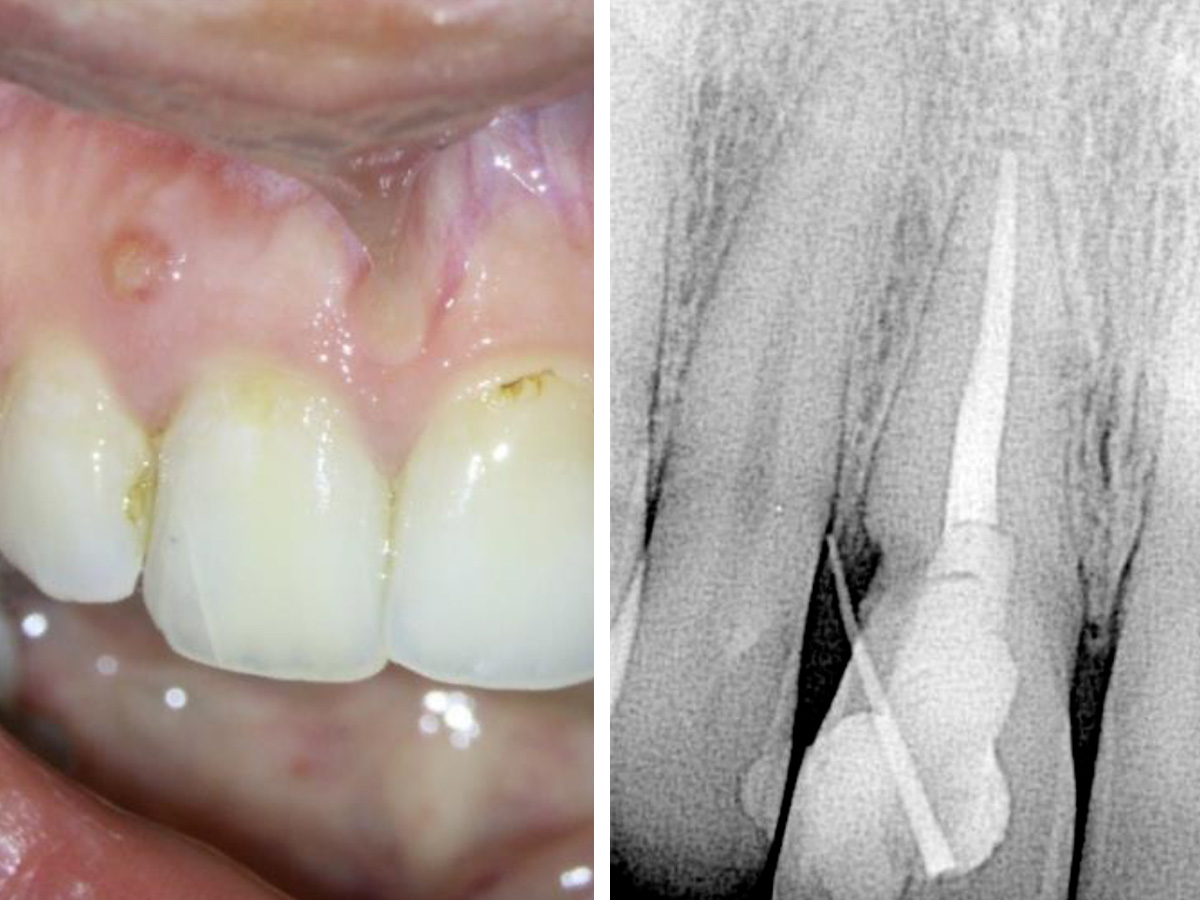

Abbildung 3

Abbildung 4

Nach zwei Wochen stellte sich die Patientin symptomfrei vor. Die Fistelöffnung war verschwunden und der resorptive Defekt blutete nicht mehr. Die Behandlung wurde fortgesetzt und erneut wurde Kalziumhydroxid in den Wurzelkanal gefüllt. Da der resorptive Defekt trocken und zugänglich war,wurde entschieden den resorptiven Defekt mit BC Putty durch die Zahneröffnung (internes Vorgehen) zu füllen (Abb. 3).

Als die Patientin nach zwei weiteren Wochen wiederkam, war keinerlei Fistelbildung zu diagnostizieren, das biokeramische Putty war immer noch an der modellierten Stelle vorhanden und schien den Defekt gut zu versiegeln. Der Wurzelkanal wurde fertiggestellt und die Zugangskavität mit einem Komposit versiegelt (Abb. 4).